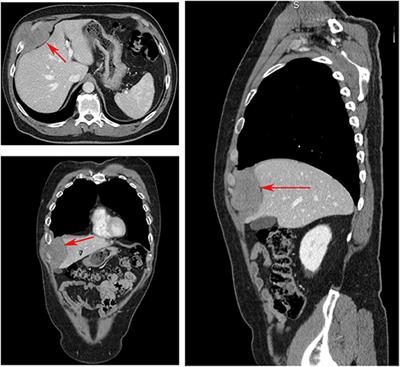

Interdisciplinary Radical “En-Bloc” Resection of Ewing Sarcoma of the Chest Wall and Simultaneous Chest Wall Repair Achieves Excellent Long-Term Survival in Children and Adolescents